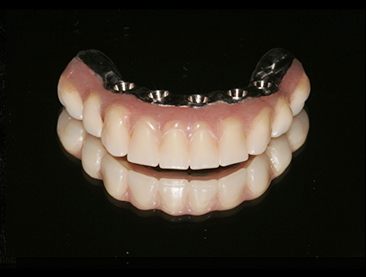

Fully edentulous clinical cases